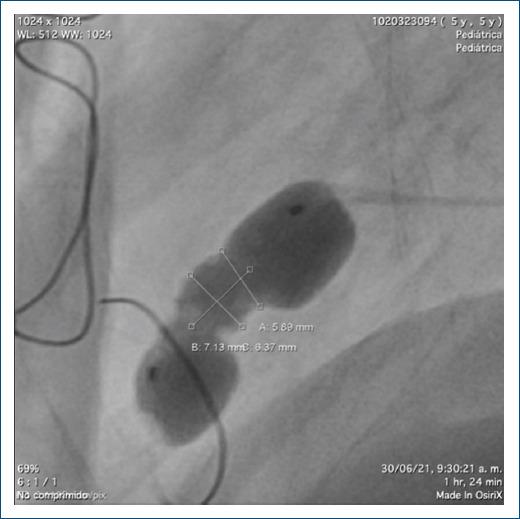

Present other management options for ventricular diverticula, different from surgical options, using alternative materials that are not used very often in daily practice.

A detailed description of a case successfully managed with these new treatment modalities.

Endovascular management of the left ventricular diverticulum, diagnosed prenatally in the patient presented, was successful after initial failure with surgical management.

提出与手术选择不同的心室憩室管理方案,使用日常实践中不常用的替代材料。

详细描述一例成功采用这些新治疗方式的病例。

本文所呈现患者产前诊断出的左心室憩室,在手术治疗初次失败后,血管内治疗取得成功。